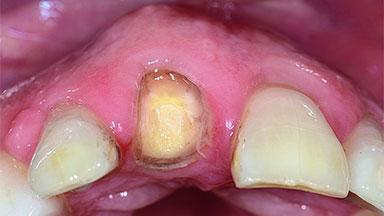

A 49-year-old female patient was referred for implant therapy to replace the upper right central incisor (tooth 11). The tooth had been assessed by an endodontist who diagnosed a vertical fracture of the root. The tooth had a hopeless prognosis and needed to be extracted. The patient was healthy and was not taking any medications. She was allergic to penicillin. The patient had high esthetic demands but her expectations were realistic. The extraoral examination revealed no facial asymmetries. The right temporomandibular joint demonstrated an opening click but was otherwise asymptomatic. The lip line was high with a significant gingival display.